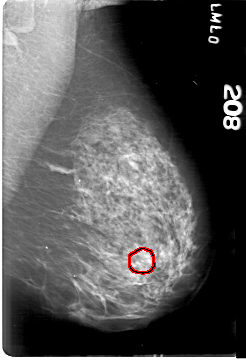

D_4164_1.LEFT_MLO

LEFT_MLO LINES 5386 PIXELS_PER_LINE 3676 BITS_PER_PIXEL 12 RESOLUTION 43.5 OVERLAY

FILE: D_4164_1.LEFT_MLO.OVERLAY

TOTAL_ABNORMALITIES 1

ABNORMALITY 1

LESION_TYPE CALCIFICATION TYPE AMORPHOUS DISTRIBUTION CLUSTERED

ASSESSMENT 0

SUBTLETY 3

PATHOLOGY BENIGN

TOTAL_OUTLINES 1

BOUNDARY